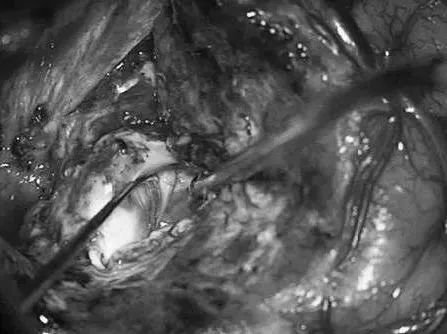

Lawton教授术中操作

左侧翼点开颅,再次手术,显露前颞叶。

沿颞下回经原皮层入路达颞角。

AChA经脉络裂进入颞角,在前方供应AVM,lPChA在后方供应AVM。

通过ITG经皮层显露可以充分显露颞角,达到全切AVM。